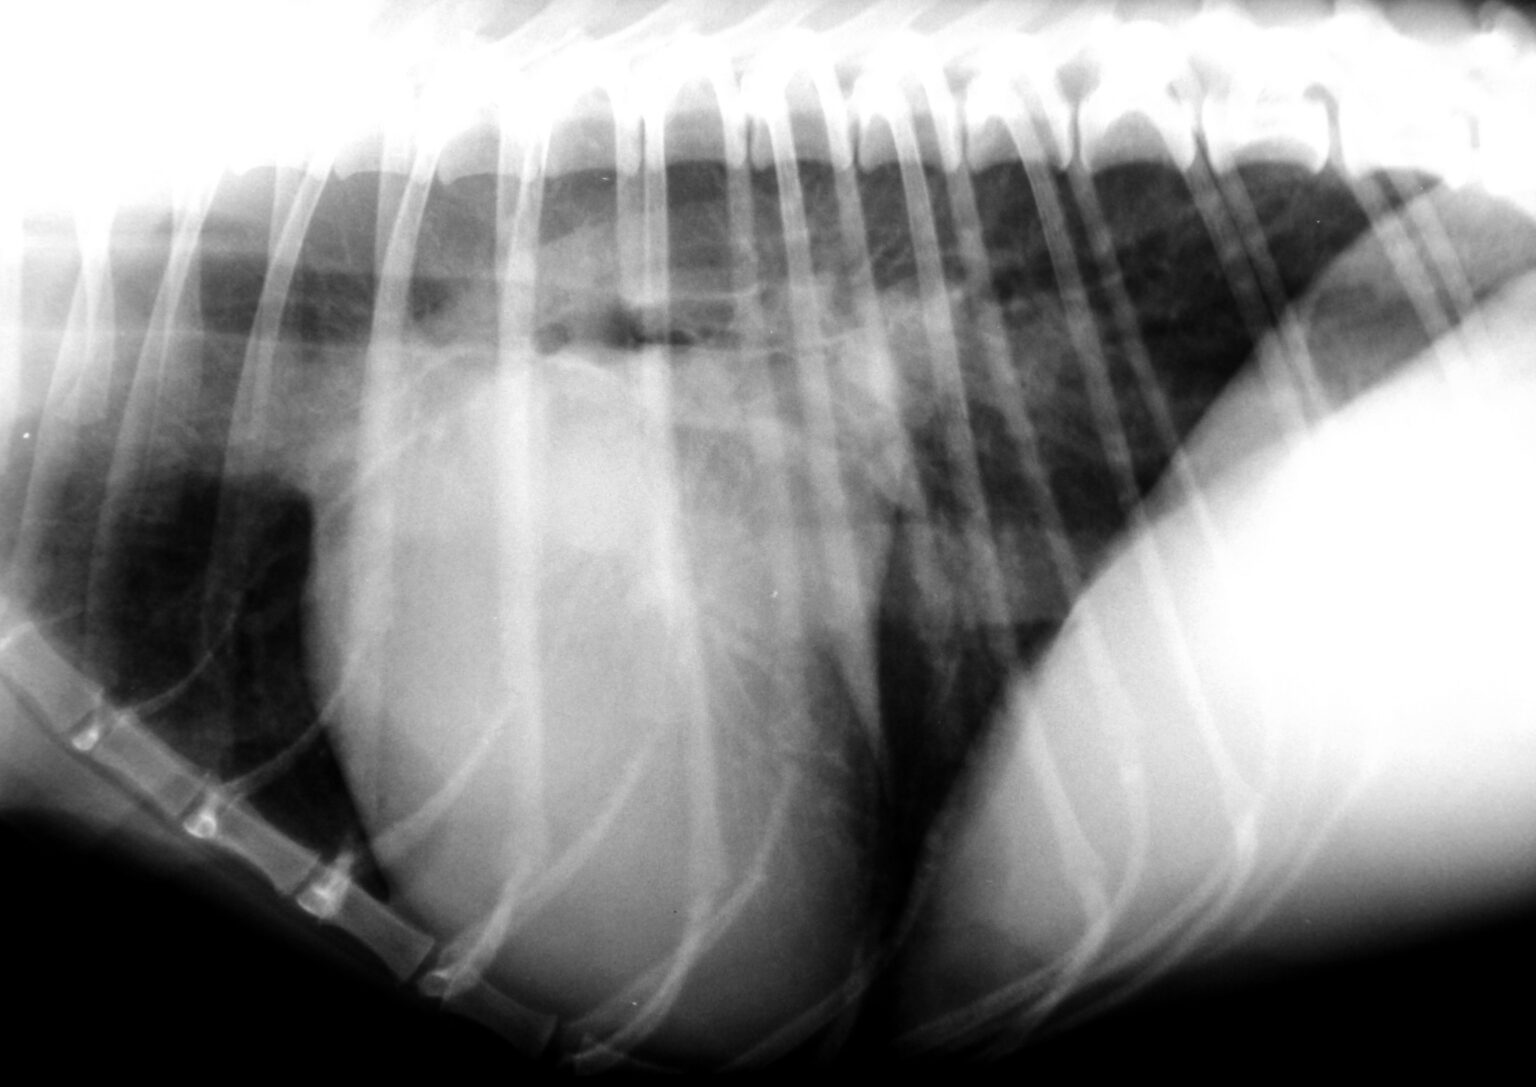

Hund Vergrößertes Herz Drückt Auf Luftröhre

Hier erfahren Sie, was Sie über Kardiomyopathie bei Hunden wissen müssen, von den Symptomen und wie sie sich auf den Körper auswirkt bis hin zu Diagnose und Behandlung. Allerdings gibt es auch Herzbeutelergüsse, Neoplasien, Arrhythmien oder Infektionen (Herzwürmer), die ein vergrößertes Herz beim Hund bedingen können.

Informationen zur Dirofilariose beim Hund Tierklinik Hofheim. Die Vergrößerung des Herzens kann zu einer Verringerung seiner Pumpleistung führen, was eine unzureichende Zirkulation von sauerstoffreichem Blut im Körper zur Folge haben kann. Schnelle Ermüdung: Hunde mit Herzkrankheiten zeigen oft eine verminderte Ausdauer